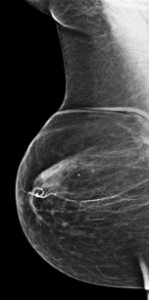

La mamografía bilateral en dos proyecciones es la primera prueba diagnóstica que se pide para el estudio de la patología mamaria en mujeres mayores de 35 años. Si la paciente tiene menos de 35 años, el método de elección es la ecografía.

Las dos proyecciones, Craneo-Caudal (CC) y Oblicua MedioLateral (OML), bilaterales, nos permiten situar la lesión, manera más precisa y completa que con una proyección unilateral.